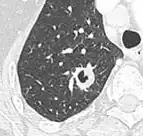

Low attenuating nodule (in this case a fat containing hamartoma).[9] -

Cavitation with relatively thick wall, in this case aspergilloma).[9]